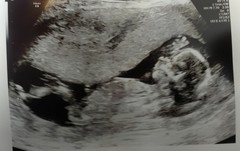

Thank you all for your good luck wishes.i am delighted and relieved to say the scan went well - baby measuring ahead again at 13+4 making due date 8th March!

Congrats @strawberrye!!! That's fantastic and amazing scan photo. Your due date is just five days ahead of mine :). Are you waiting for test results now? Xxx

@strawberrye that scan is lovely, baby looks quite chilled in there

@strawberrye that's a lovely clear picture. Congratulations!